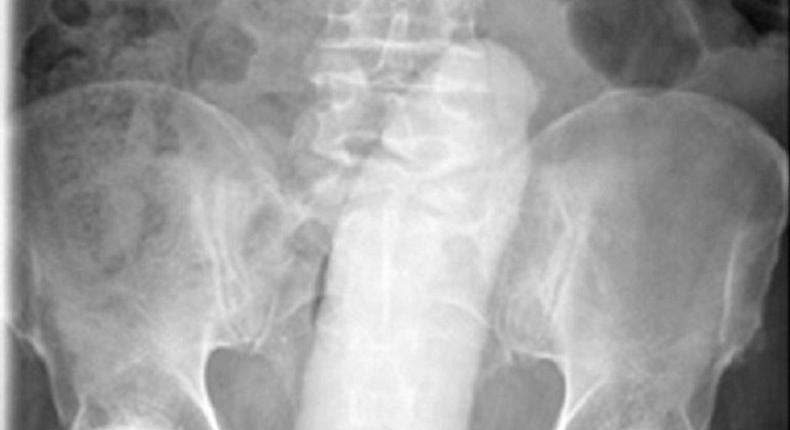

The scanned image of thee dildo in the man's rectum

According to the International Journal of Surgery Case Reports, the man was using the dildo for sexual gratification when it slipped and went into his rectum.

The pensioner had to be rushed to the Mater Hospital where doctors spent 10 hours trying to remove the 23cm sex toy.

After the doctors failed to remove the toy, they gave the man a general anaesthetic so they could successfully extract the dildo using forceps.

'A 68-year-old man presented to the emergency department with severe lower abdominal discomfort, distension and inability to pass urine, flatus or bowel motions.

He had inserted a phallic object in the rectum ten hours prior to presentation and had been unable to remove same.

Following a manual attempt at removal in the emergency department, a decision was made to remove this under anaesthesia due to worsening symptoms

The phallic object was successfully removed under general anaesthesia using a pair of Magill’s forceps.”'The report said people had previously used bottles, light bulbs, apples, rubber balls, spray containers, vibrators, and other phallic objects such as sex toys.